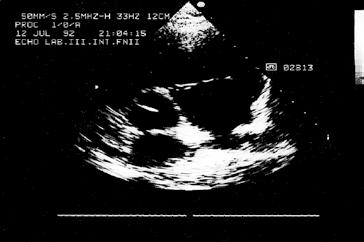

Kromě nakladatelství a výtvarníka se o definitivní podobu třetího dílu učebnice zasloužili mnozí odborníci. Za poskytnutí rtg snímků jsem již od vzniku 1. vydání 3. dílu učebnice vděčný Radiodiagnostické klinice 1. LF UK a paní doc. MUDr. Běle Drugové, DrSc., z radiodiagnostického oddělení Nemocnice Na Homolce. Za vynikající mikrofotografie z vývoje oka děkuji panu prof. MUDr. Františku Vrabcovi, DrSc., který mi je poskytl pro tuto knihu. Panu prof. MUDr. Oldřichu Eliškovi, DrSc., a paní doc. MUDr. Miloslavě Eliškové, CSc., děkuji za poskytnutí podkladů z jejich studií pro vytvoření obrazů mízního odtoku ze srdce. Panu doc. MUDr. Jaromíru Hradcovi, CSc., ze III. interní kliniky 1. LF UK děkuji za poskytnutí echokardiografických obrazů srdce. Upřímně děkuji též oběma spolupracovníkům, panu prof. MUDr. Rastislavu Drugovi, DrSc., a panu prof. MUDr. Miloši Grimovi, DrSc., za porozumění a sympatickou spolupráci na tomto vydání knihy. Studentům, učitelům anatomie i lékařům přeji, aby jim kniha sloužila jako užitečný průvodce a pomocník při studiu tohoto náročného oboru.